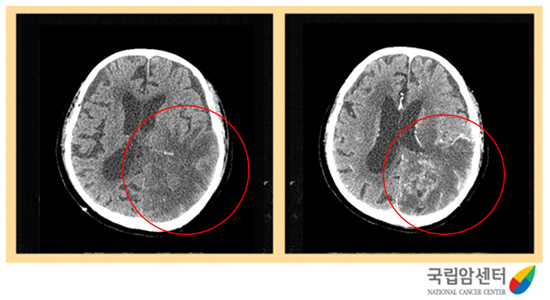

교모세포종의 뇌 전산화단층촬영 소견

2009.12.16